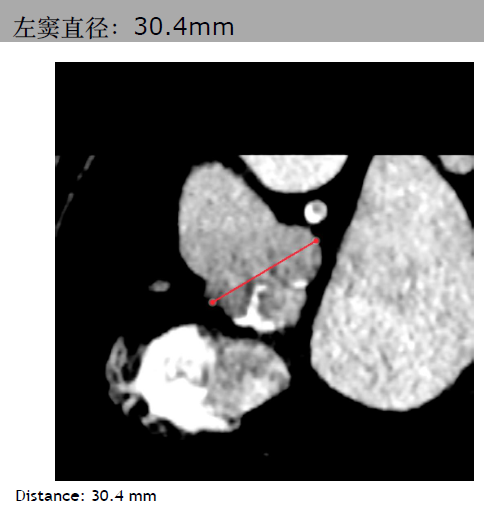

三叶瓣,主动脉瓣环平均直径21.3mm。右冠脉高度10.3mm,右窦直径:28.4mm。左冠脉高度14.1mm,左窦直径:30.4mm。STJ平均直径25.4mm,高度17mm。